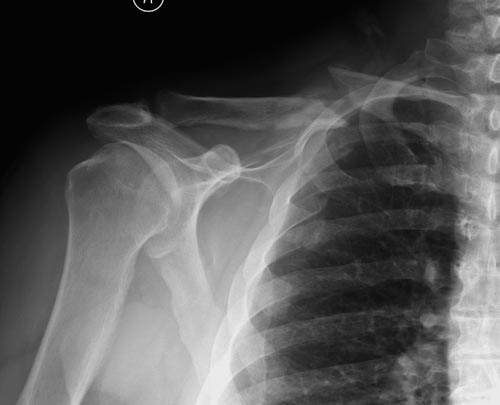

Уважаемые коллеги. Обратился пациент 29лет, оперирован в 2007 г. в Республиканском центре по поводу перелома ключицы и/м спицей, после несращения повторно оперирован в 2008 году, со слов больного освежение и повторно фиксация спицами, и обратился только через 6 лет, активные и пассивные движения в правом плечевом суставе в полном объеме, беспокоит только слабость при поднятии тяжести и подвижность в с/з ключицы. Р-снимок прилагается.Честно признаться, пока не знаю, что делать, имеются обычные пластины из ЦИТО, спицы, может, краевая резекция до появления «росы» дефект заполнить спонгиозной костью, фиксация и/м двумя спицами, загнуть оба конца спицы с компрессей, или пластина…или вообще не трогать. Прощу не критиковать, имеем то, что имеем, пациент в НИИТО не может ехать из-за финансов. С уважением Абдурашид.

Оставлять так однозначно нельзя. Сам по себе ложный сустав не срастется. По поводу спиц думаю, что если с двух попыток не решили проблему, не решат и в третий раз, так как не обеспечивают стабильный остеосинтез.

Краевая резекция до появления "росы", заполнить дефект аутокостью, стабилизировать отломки пластиной с у/с максимально атравматичным способом. На мой взгляд оптимальное решение.